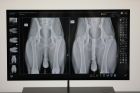

SolidDR CX

Systemet är en Medivet-byggd lösning där vi själva har valt komponenter och optimerat både applikation, funktion samt bildresultat.

- Grundläggande och kompletta funktioner

- Vara enkelt att använda

- Leverera en hög och stabil bildkvalitet

- Innehålla senaste tekniken